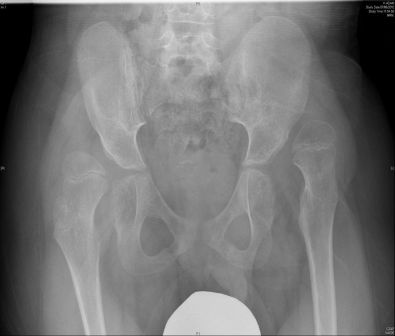

This child had bilateral hip surgery and soft tissue releases by Dr Zenios in one surgery